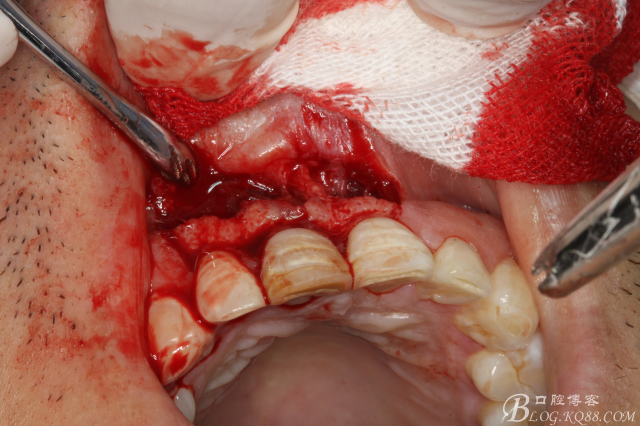

圖16.骨腔放置膠原蛋白海綿

圖17.膠原蛋白完全填滿骨缺損區(qū)域